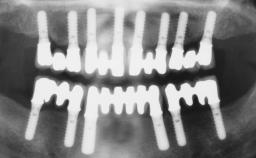

| Case Type | Single-Tooth Space |

| Jaw | Maxilla |

| Area | Anterior |

| # of Teeth | 1 |